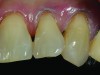

A 55-year-old woman presented with root decay along the left lateral incisor (tooth No. 10) and canine (tooth No. 11) (Figure 1). It was proposed that invisible Class V restorations be placed using an MMID procedure. There are several keys to attaining a successful invisible Class V restoration. Proper understanding of composite resin shade selection, preparation design, and sequence of composite resin layering are important to achieve an ideal blending of the composite resin to the existing tooth. Correct finishing and polishing technique is equally essential in obtaining a seamless esthetic restoration.3,11

Total removal of the decay was performed. To keep the preparation minimally invasive, a caries indicator (Seek®, Ultradent Products, Inc., www.ultradent.com) was used so that only the infected dentin was removed. Minimally invasive burs (Micro Prep Kit, Komet USA, www.kometusa.com) were used, which are helpful when minimal tooth removal is an objective (Figure 3). A long-bevel margin (889M-007, Komet USA) was then created along the facial side so that the final composite resin could be blended to the existing dentition. A thin layer of resin-modified glass ionomer (RMGI) (GC Fuji II™ LC, GC America Inc.) was sculpted and light-cured to cover the affected dentin.